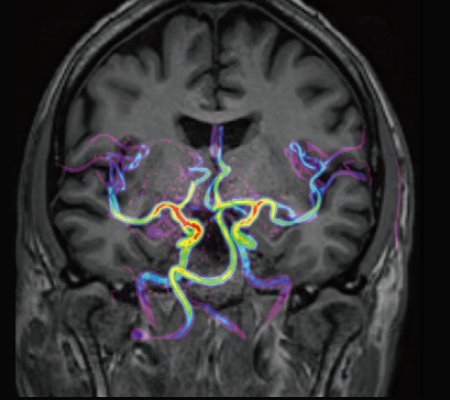

• Kopplung von mUTE und mASTAR ermöglicht 4D-Angiografie mit Auflösung einer TOF ohne Kontrastmittelgabe